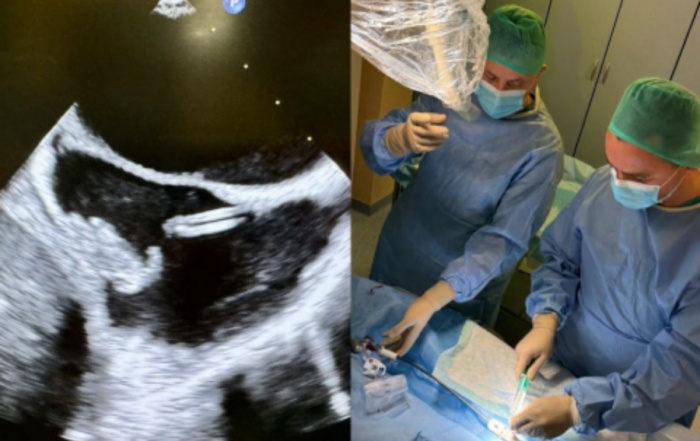

Pierwsze fizjologiczne wszczepienie układu stymulującego u dziecka w UCK WUM

W Klinice Kardiologii Wieku Dziecięcego i Pediatrii Ogólnej UCK WUM, kierowanej przez prof. Bożenę Werner, u 9-letniej dziewczynki z niewydolnością [...]